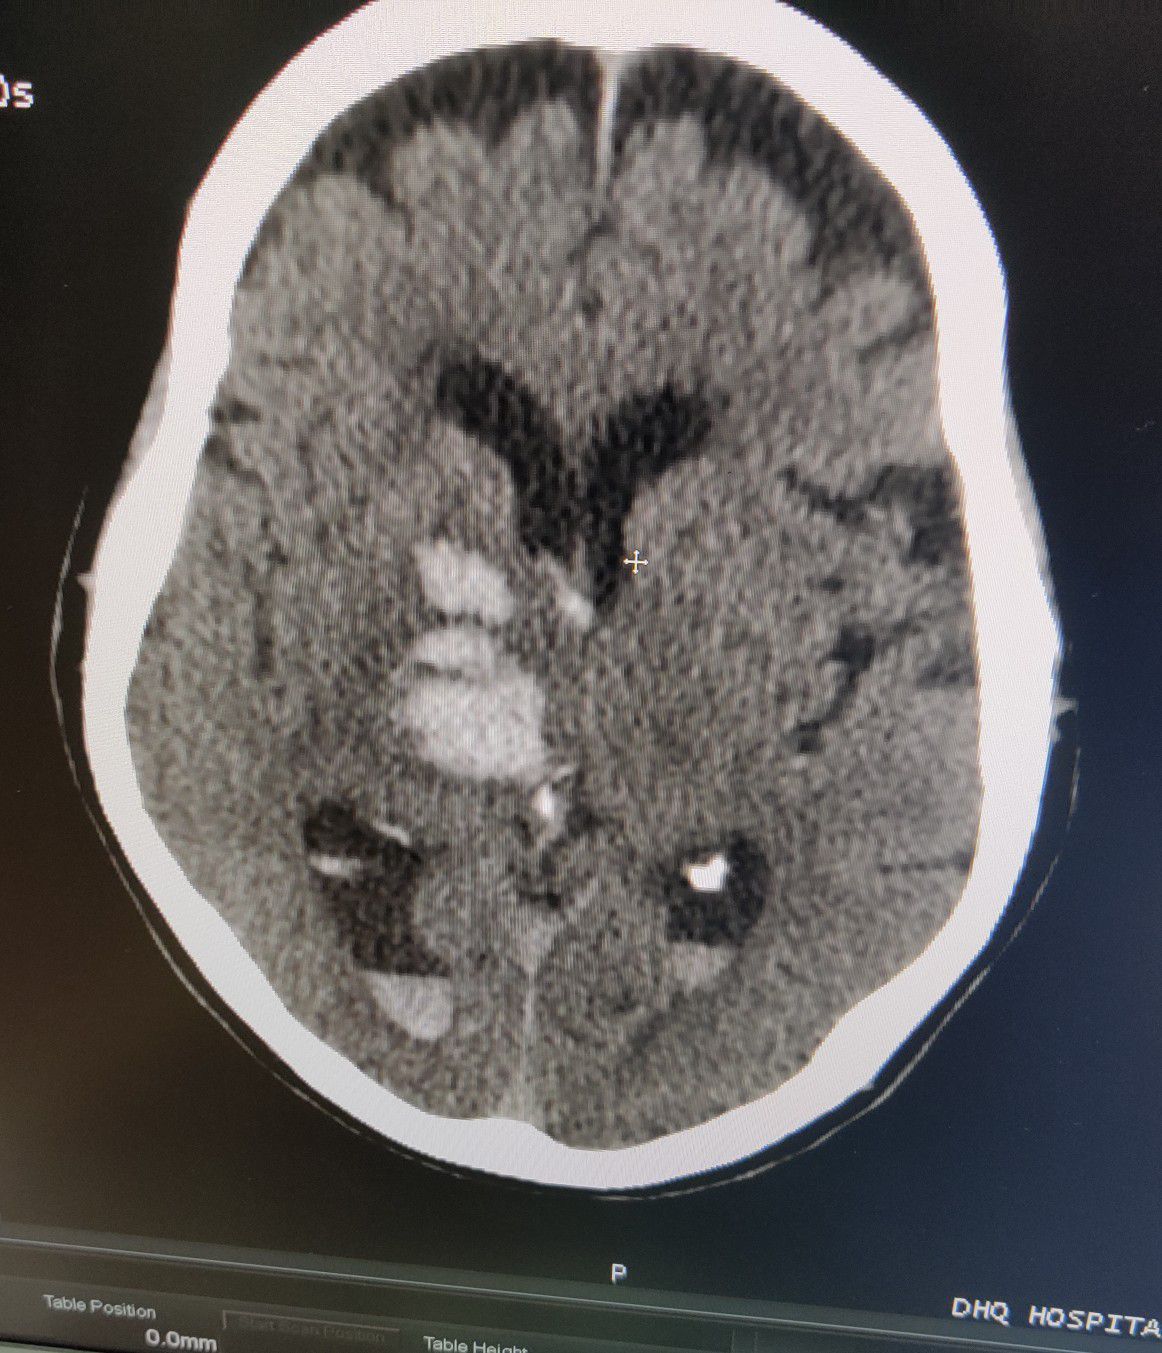

Hemorrhagic CVA

Stroke

Cva

Hemorrhagic